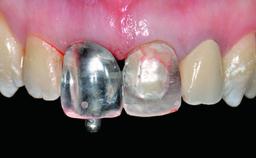

Replacement of a Compromised Upper Right Central Incisor: Hard- and Soft-tissue Augmentation, Late Placement of an RC Bone Level Implant

Abutment Type CAD/CAM

Prosthesis Type FDP

Loading Protocol Conventional or early

Retention Screw-retained Screw-retained

Provisional Implant-Supported Prosthesis Prosthodontic margin > 3 mm apical to mucosal margin Prosthodontic margin > 3 mm apical to mucosal margin